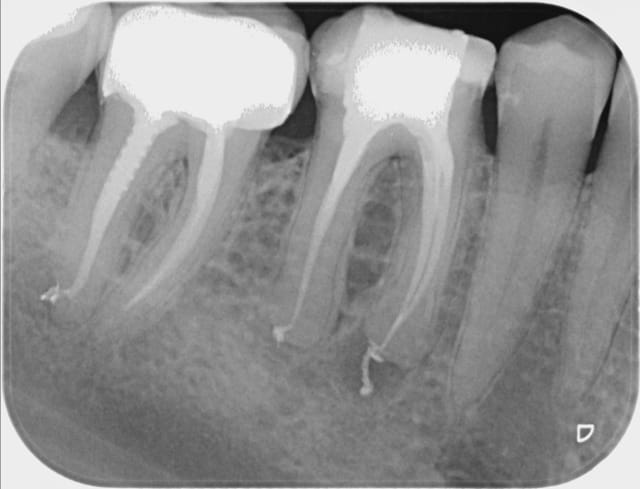

vu la pré op j'avais très peur du résultat mais avec des limes 10 puis 15 avec du glyde et beaucoup de patience, c'est passé! je suis pas mécontent du résultat sur ce truc qui sommeille depuis 40 ans

Bonjour , pourriez vous m'expliquer l'excès de produit au niveau de l'apex au niveau des racines obturées , c'est un dépassement ? Merci .